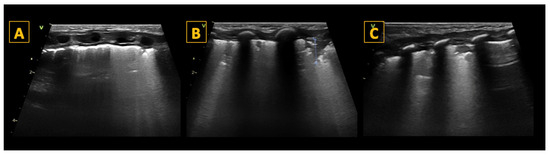

5.4.2. B-Lines

5.5. Consolidations